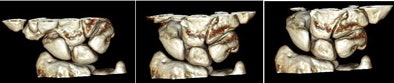

The still images were also useful, Leng said. Carpal bones, distal radius and ulna, and joint spaces were clearly delineated in the reconstructed 2D images and 3D images, and there was no motion blurring or banding artifacts. A hand surgeon judged the images to be of excellent quality.

![]() |

| Volume-rendered images of cadaver wrist in radial deviation, neutral, and ulna deviation positions show individual carpal bones and joint spaces clearly in three dimensions. All images courtesy of Shuai Leng, PhD. |